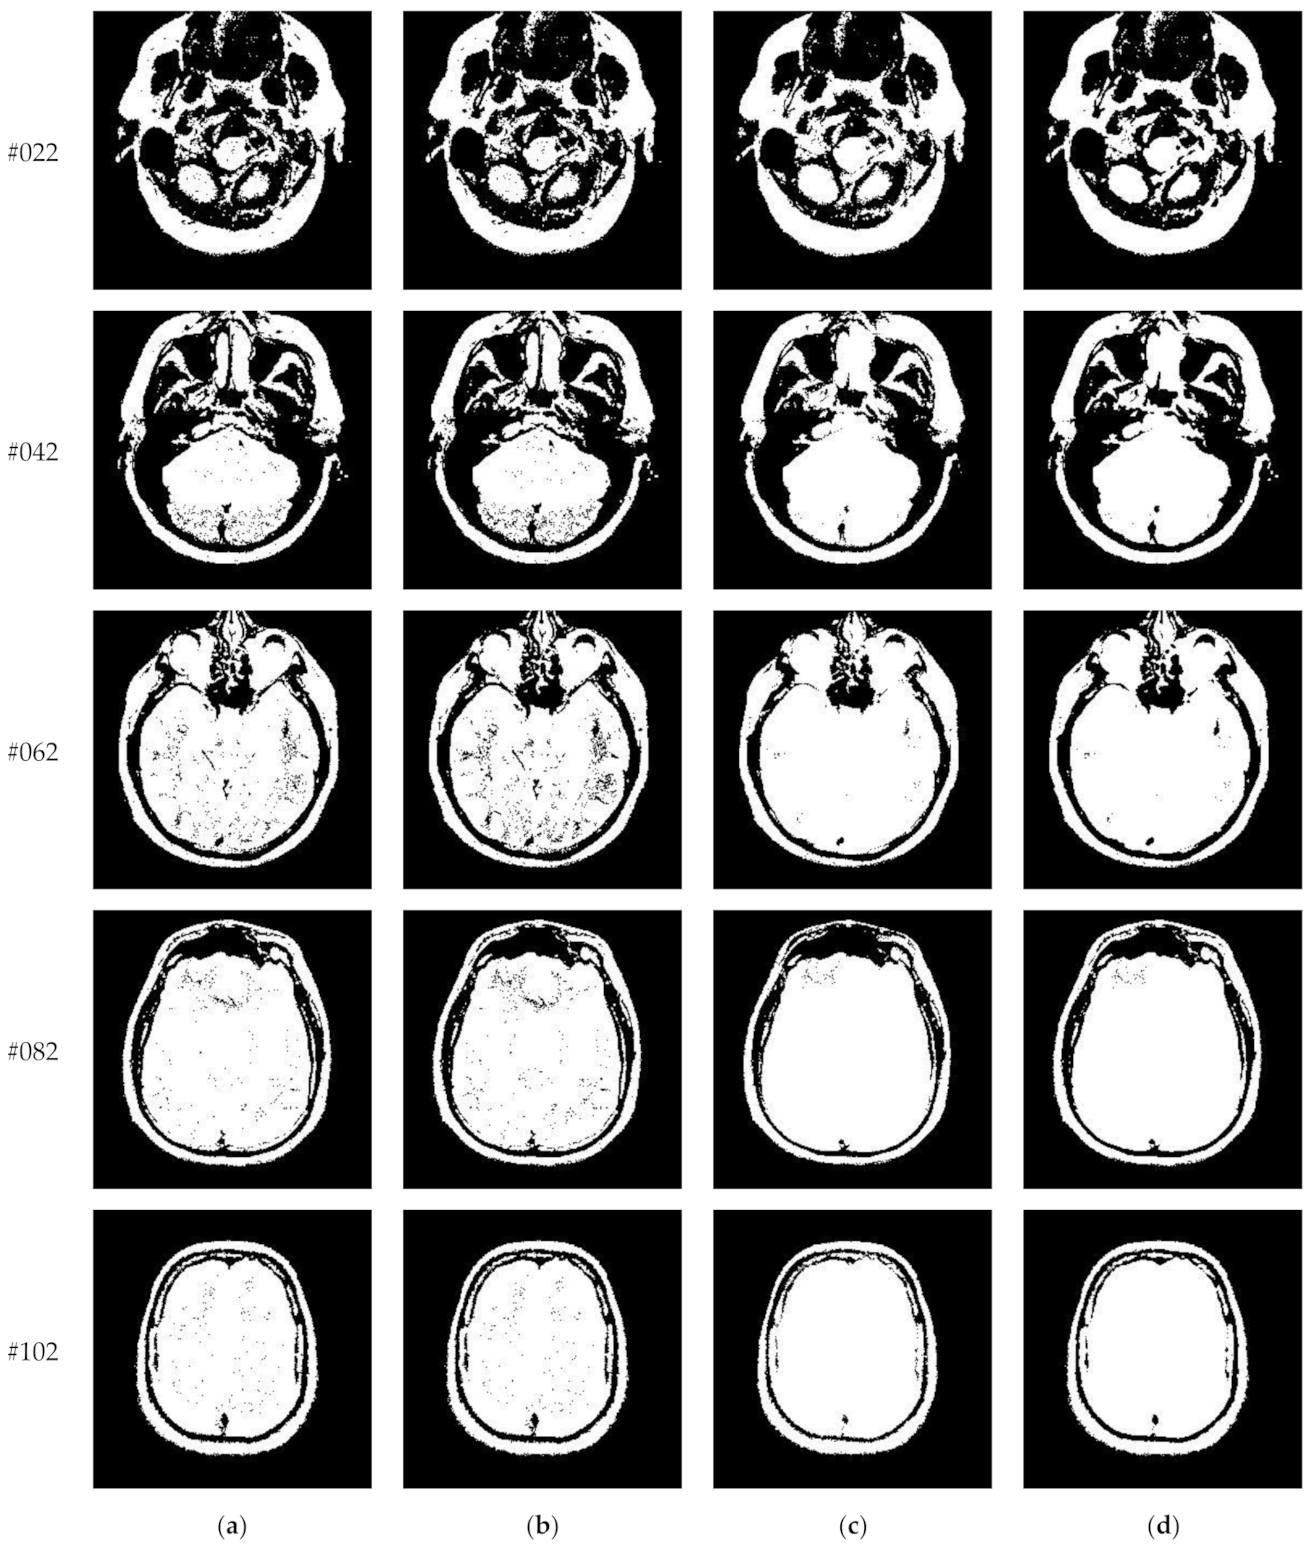

Figure 10 and Figure 11 display segmentation results of different algorithms for slice #042 and slice #082, respectively. For single level of thresholding K = 1, it can be observed that segmentation results obtained by the Otsu method have many fragmented small areas, such as the lower soft tissue in the first row of Figure 10a, whereas IIMT performs slightly better. However, the edges segmented by HL-IIMT and Proposed are much clearer. In the case of , it can be seen that Otsu and IIMT have similar segmentation effects. HL-IIMT and Proposed are better than Otsu and IIMT in terms of edge-preserving and denoising, as shown in the segmentation results in Figure 11 (K = 2, K = 4).

Figure 10.

Segmentation results obtained by different segmentation algorithms for slice #042 with number of thresholds K from 1 to 5: (a) Otsu, (b) IIMT, (c) HL-IIMT, (d) Proposed.

Figure 11.

Segmentation results obtained by different segmentation algorithms for slice #082 with number of thresholds K from 1 to 5: (a) Otsu, (b) IIMT, (c) HL-IIMT, (d) Proposed.

Figure 14 displays the segmentation results of images containing noise with a single level of thresholding K = 1. It can be observed that segmentation results achieved by HL-IIMT and Proposed are distinctly better than those of Otsu and IIMT, which have many isolated points. Figure 15 depicts segmentation results obtained by different algorithms with multilevel thresholding K = 4. Obviously, segmentation results of Otsu, IIMT, and HL-IIMT are seriously affected by noise, and most regions are blurred. However, the results of Proposed are better, and they have less noise and clearer edges.

Figure 14.

Segmentation results obtained by different segmentation algorithms for images containing noise (K = 1): (a) Otsu, (b) IIMT, (c) HL-IIMT, (d) Proposed.

Figure 15.

Segmentation results obtained by different segmentation algorithms for images containing noise (K = 4): (a) Otsu, (b) IIMT, (c) HL-IIMT, (d) Proposed.